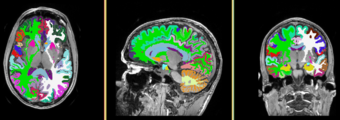

=Result= | =Result= | ||

Image:MRIHumanBrainFullParcellationT1 Labelmap.png | Image:MRIHumanBrainFullParcellationT1 Labelmap.png | ||

Single channel automatic segmentation of t1w-MRI brain scans into the major tissue classes (gray matter, white matter, csf). The task can only be applied to t1w brain scan showing parts of the skull and neck. The pipeline consist of the following steps:

Anatomical Tree

- root

- background (BG)

- air (AIR)

- skull (skull)

- intracranial cavity (ICC)

- white matter (WM)

- grey matter (GM)

- cerebrospinal fluid (CSF)